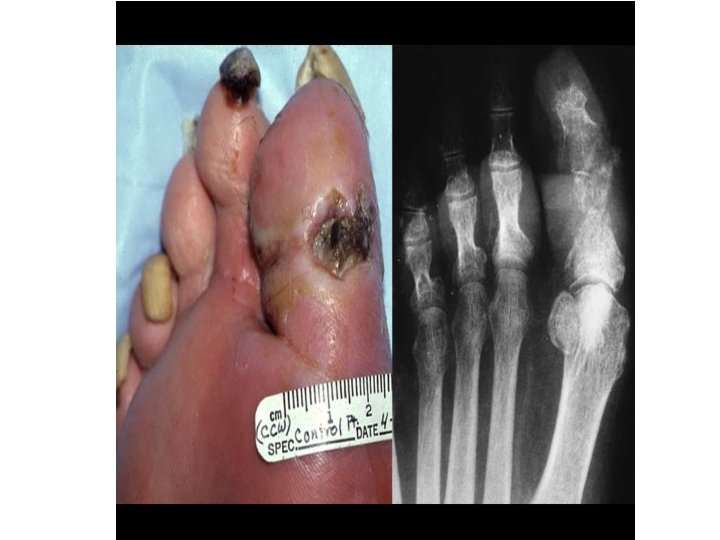

Chronic osteomyelitis • • • • In 5% to 25% of cases, acute osteomyelitis fails to resolve and persists as chronic infection. • Chronic infections may develop when there is delay in diagnosis, extensive bone necrosis, inadequate antibiotic therapy or surgical debridement, or weakened host defenses. • The course of chronic infections may be punctuated by acute flare-ups; these are usually spontaneous and may occur after years of dormancy. • Other complications of chronic osteomyelitis include pathologic fracture, secondary amyloidosis, endocarditis, sepsis, and development of squamous cell carcinoma in the draining sinus tracts and sarcoma in the infected bone.

Management • Antibiotics for at least one month • Surgery (drainage of bus ) esp. . ( failure of conservative treatment ) • Amputation esp. in ischemia &risk of sepsis